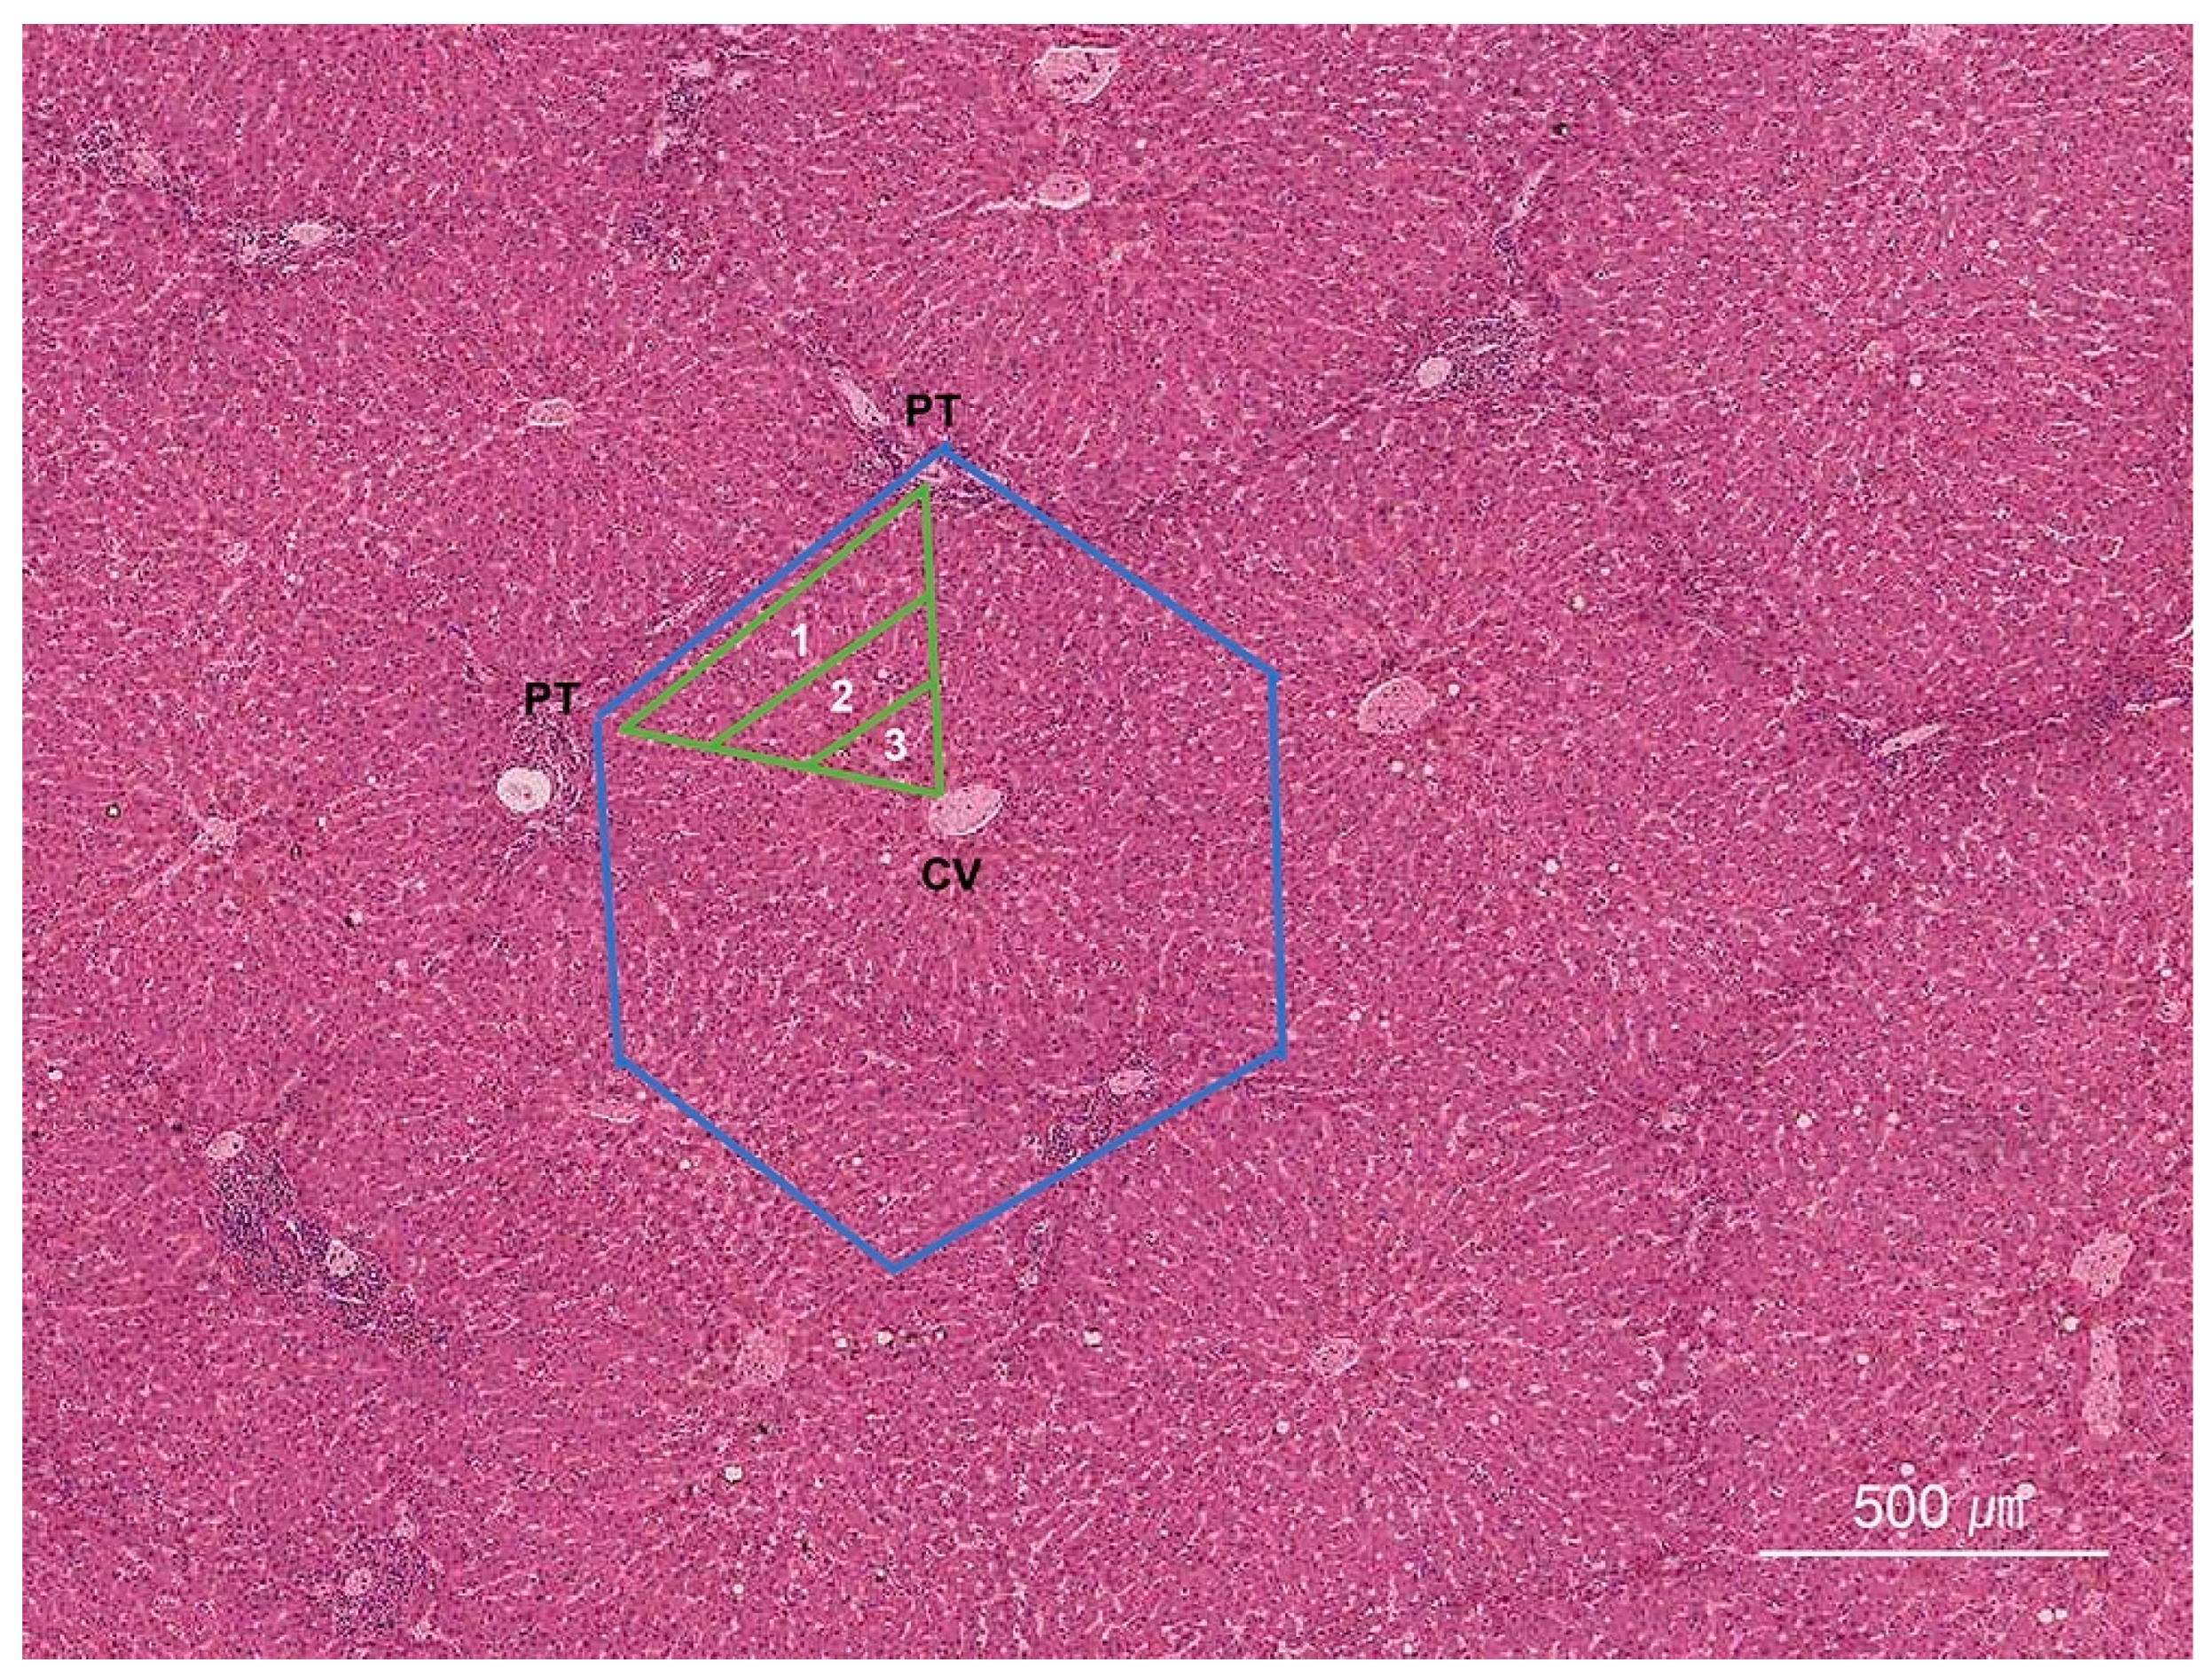

2. Normal Histology of the Liver